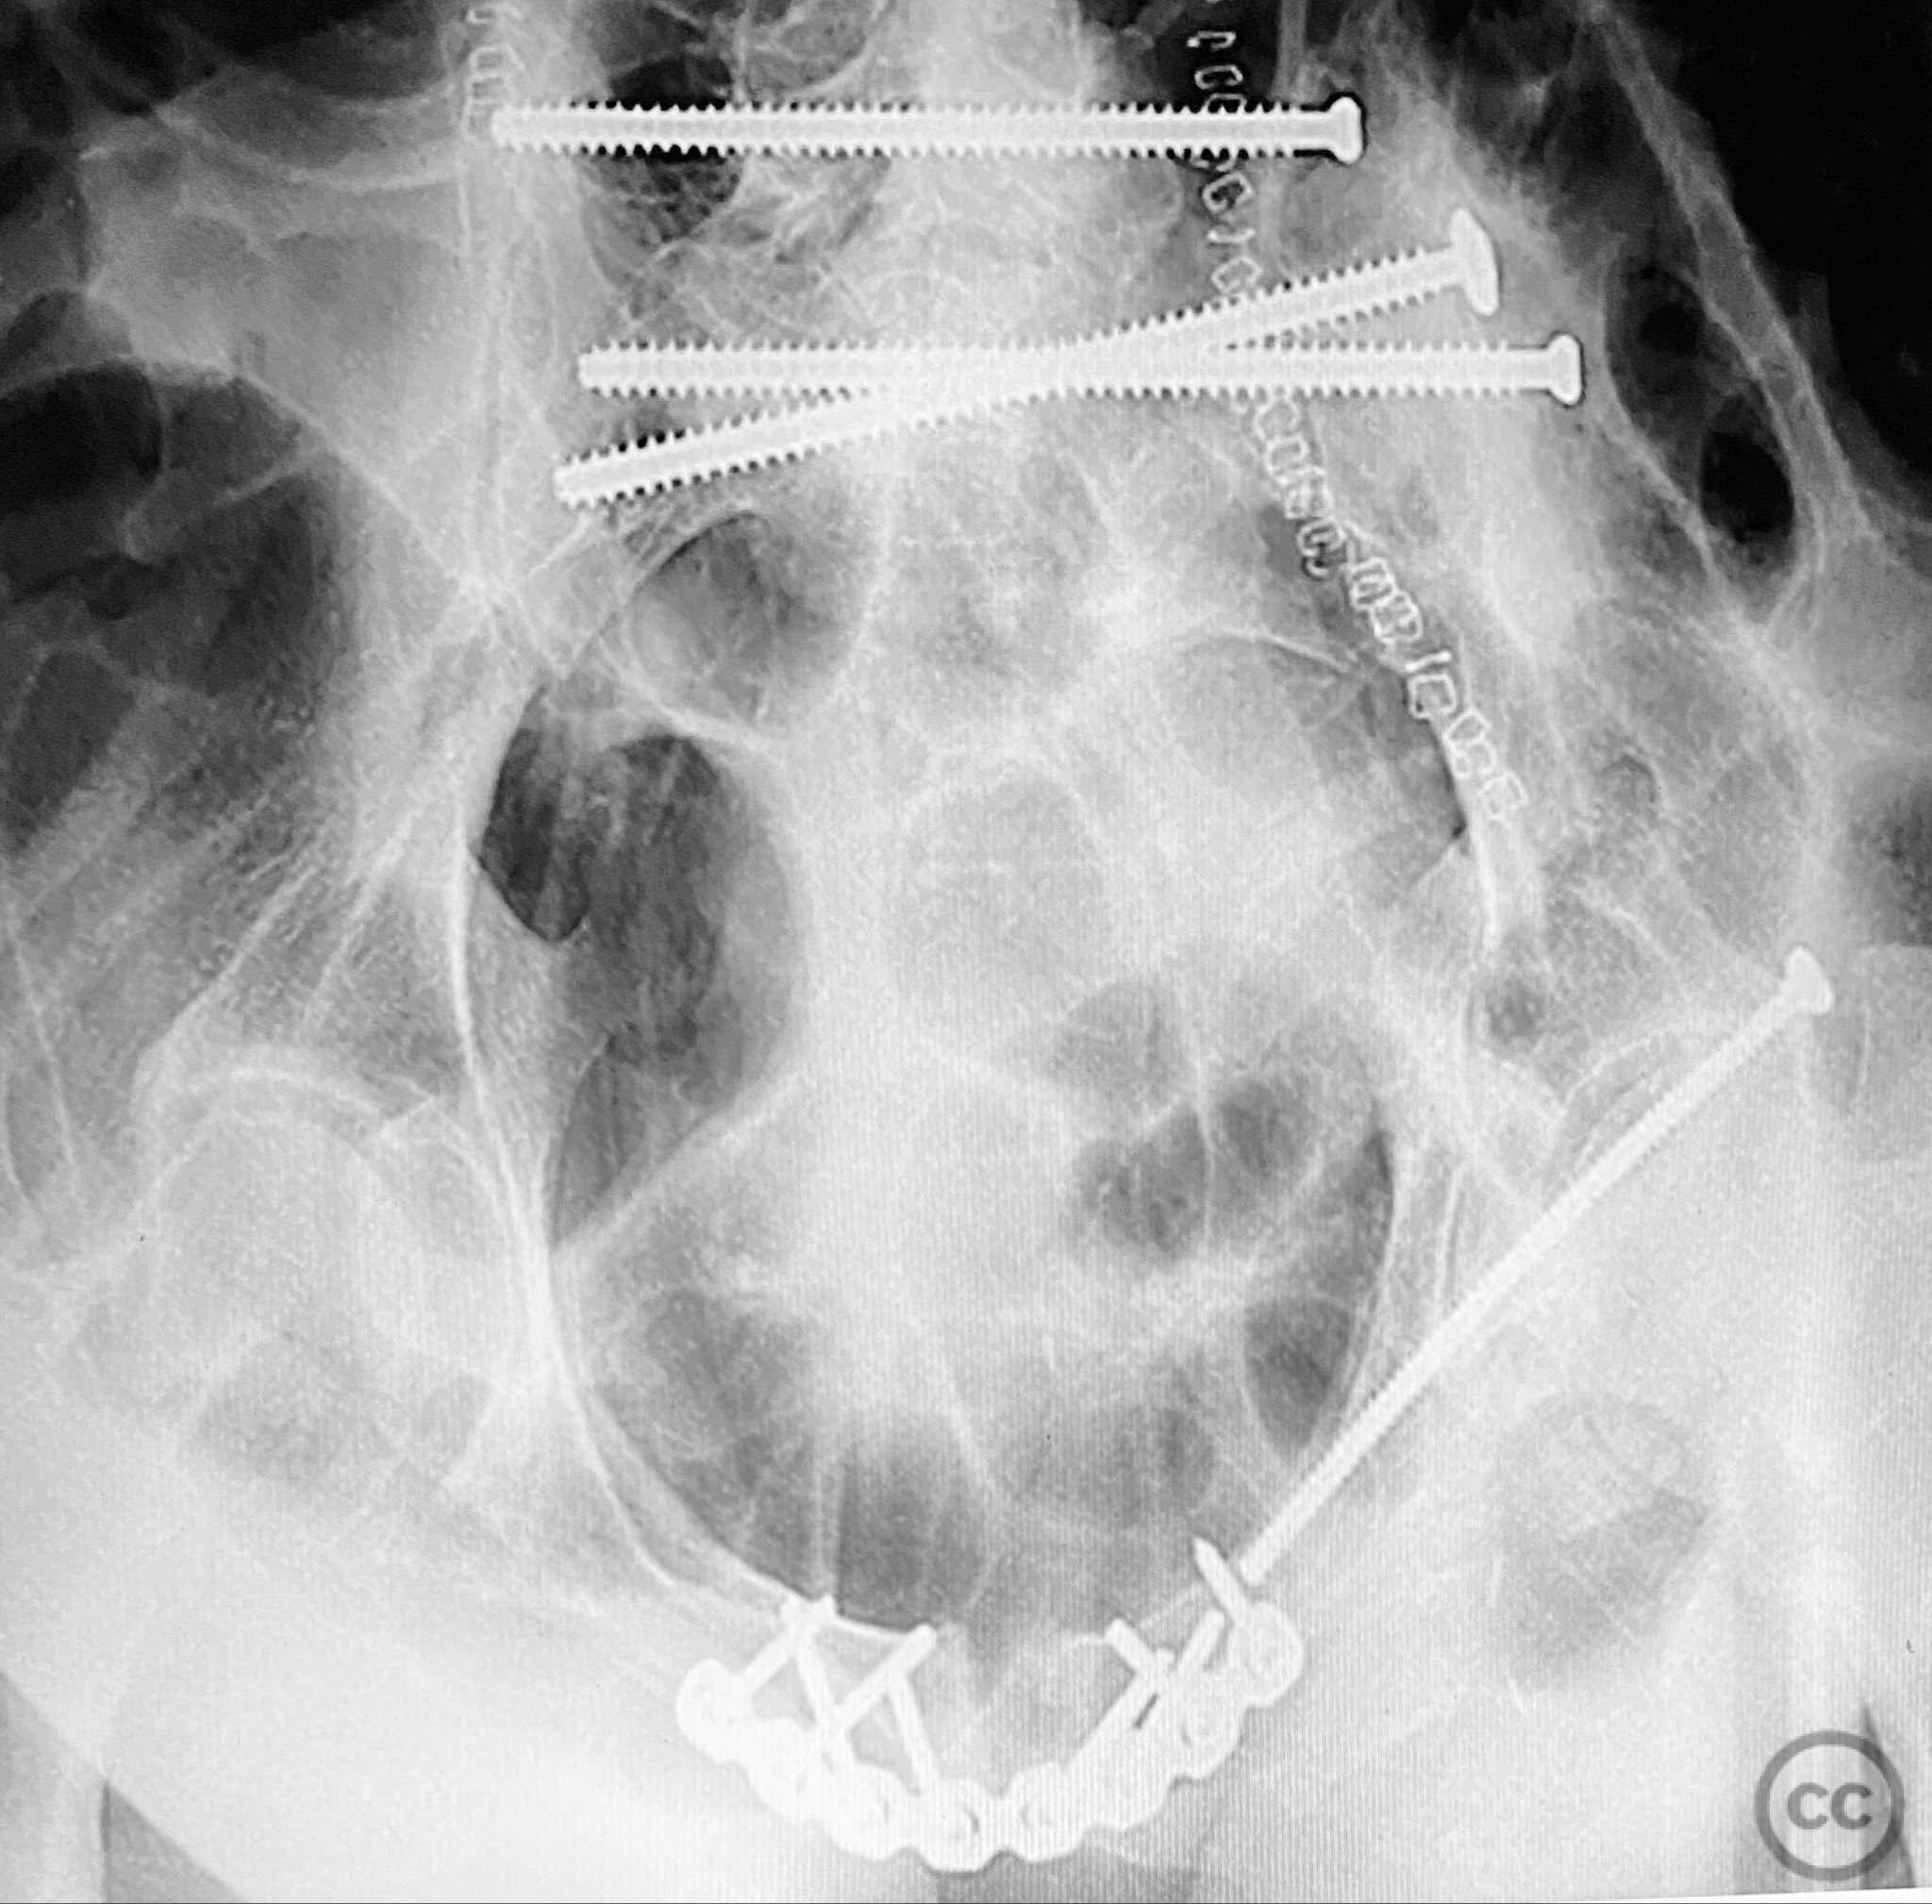

Anatomical surgical approach:  The posterior approach involved a midline longitudinal incision over the sacrum, subperiosteal dissection to expose the dorsal sacral cortex, and direct assessment of fracture reduction using the cortical edges as reference points. Reduction was achieved and maintained with clamps. Iliosacral screws were inserted percutaneously under fluoroscopic guidance, supplemented by a posterior transiliac screw traversing from one ilium to the contralateral ilium across S1/S2. The anterior approach utilized a Pfannenstiel incision for exposure of the symphysis pubis and adjacent rami; reduction was achieved with pointed reduction forceps and stabilized with a symphyseal plate and additional ramus screws as indicated.

The posterior reduction was facilitated by direct visualization of the dorsal sacral cortex, allowing precise assessment and clamping of the comminuted fragments prior to screw fixation. The iliosacral screws were placed without cannulated instrumentation longer than 130mm, reflecting historical implant limitations at the time of surgery. Postoperative CT confirmed satisfactory reduction and fixation of the posterior ring, though suboptimal positioning of iliosacral screws was noted (contained within the osseous fixation pathway but not optimized for maximal safety or precision). The anterior ring was subsequently addressed in a staged fashion, with anatomical reduction and stable fixation achieved via open technique. This case highlights technical challenges in achieving optimal screw trajectory and length, particularly with historical implant constraints, as well as the importance of staged management in complex pelvic ring disruptions.

Orthopaedic implants used:   7.3mm iliosacral screws (non-cannulated), posterior transiliac screw, anterior symphyseal plate, cortical screws for ramus fixation